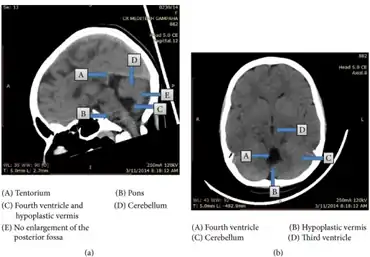

Criteria and classification

The precise diagnostic criteria and classification systems of DWM are not agreed upon, and significant dispute exists as to which terms or criteria should be used.[5][6][12] The core criteria of DWM are hypoplasia of the cerebellar vermis and an enlarged fourth ventricle and posterior fossa (the space behind the cerebellum), though the specific degree of hypoplasia or cystic enlargement for diagnosis of DWM is not agreed upon.[7] Additionally, there are several similar conditions which have at various times been grouped with DWM on a continuum by some authors and separated as distinct by others, further complicating diagnosis.[6][8]